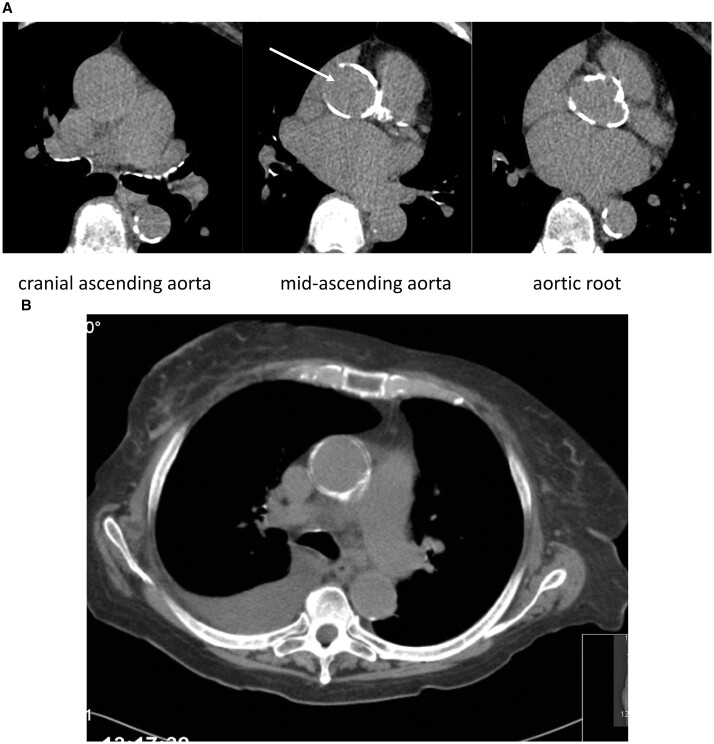

瓷主动脉不是主动脉瓣和/或冠状动脉旁路移植术的绝对禁忌症,但它需要一个特殊的策略和个体化的方法来减少栓塞并发症的风险和在打开和/或关闭主动脉切开术期间的技术问题。

Porcelain aorta is not an absolute contraindication for aortic valve and/or coronary bypass grafting but it requires a special strategy and individualized approach to minimize the risk of embolic complications and technical problems during opening and/or closing the aortotomy.